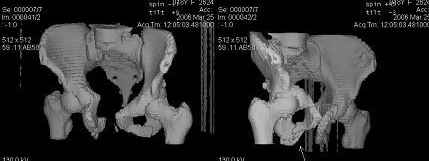

Предоставляю срезы. Если пациентку функционально ничего не беспокоит, стоит ли навязывать ей лечение.

Но если девочка более активна в жизни, я бы рекомендовал ликвидировать укорочение и вернуть тазу естественную форму.